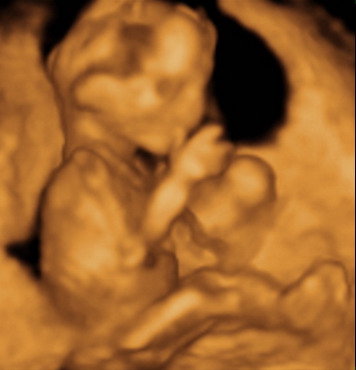

Gratula a kukishoz! Úgy tűnik minden Kisfiúnak ez a szokása! Apa akkor nagyon büszke :lol: :lol: ! Rajta múlt :D ! Kép KUKAC

Kép levitáció Kép Orr+fülfogás

Kép BOX

Kép Lúdtalp nincs :):)lábfej torna Kép Kép Álmos vagyok

Kép guggolás Kép Tipikus pasi-láb között matatás

Kép Nyújtózás

Kép Hello Kép Elég volt, most már alszom